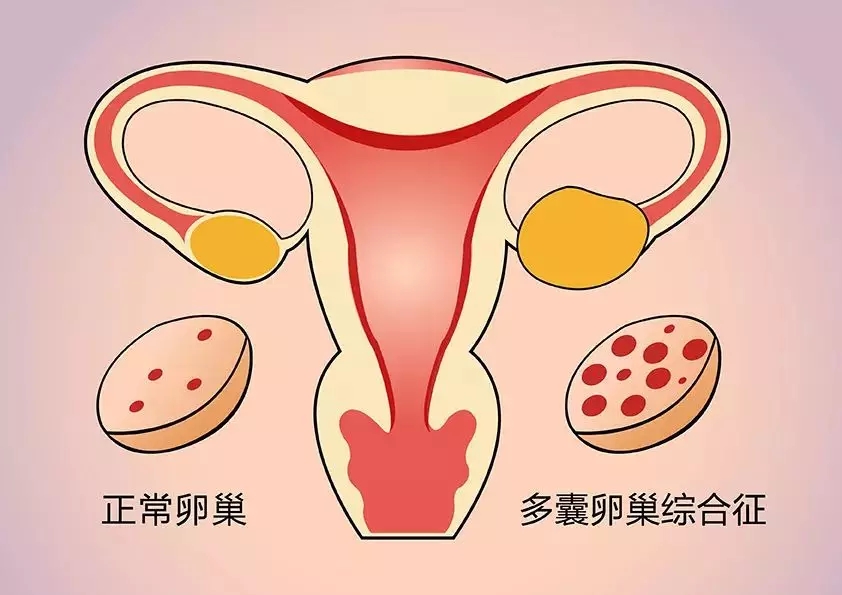

Q5备孕检查时发现多囊卵巢综合征、腺肌症、子宫肌瘤等,这些问题会对怀孕产生影响吗?

这些问题在育龄妇女中是很常见的,比如说多囊卵巢综合征,如果患者月经出现了问题,就说明她排卵也有问题,这一部分人想要怀孕的话必须找医生。

Q7举例来说,多囊卵巢综合征的患者该如何备孕呢?

有的多囊卵巢综合征患者来到医院后会说,我结婚了多少年但是一直没怀孕,现在月经也不好。之后通过化验和辅助检查,我们医生才能判断这个患者有多囊卵巢综合征。

其实多囊卵巢患者是没有成熟卵的,是不会怀孕的,经过医生的调整、治疗后才能怀孕,这样的案例我们也有很多。还有一部分多囊卵巢患者是偶发地排卵导致怀孕的,但是由于她的基础状态没有调整好,在怀孕的过程中可能会流血,甚至流产。

尤其是对于胖型的多囊卵巢综合征患者,我们医生希望她们在怀孕前最好来就医,让医生做一个生殖的评估和孕前的调整,把机体调整到最佳状态,这时怀孕才是最好的。